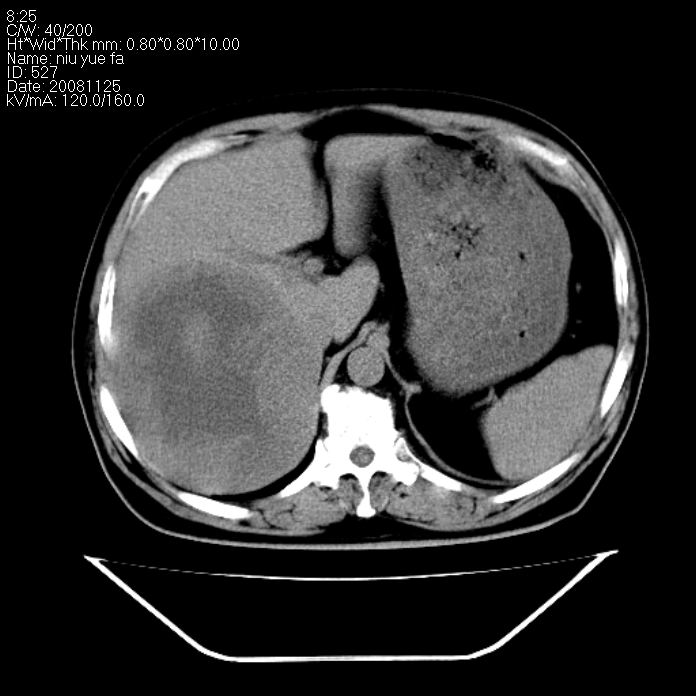

巨块型肝癌,坏死,出血;胆囊结石

1)考虑肝右叶巨块型肝癌并坏死、出血;建议行ct增强扫描检查进一步明确诊断。2)胆囊结石,胆囊炎。

考虑肝右叶巨块型肝癌并坏死、出血;建议行ct增强扫描。胆囊结石。

肝右叶巨块型肝癌并坏死、出血;胆囊结石,胆囊炎。